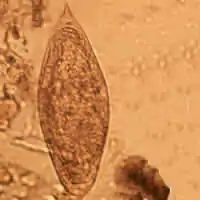

Schistosoma intercalatum

É um verme achatado parasita abobrinha do filo platyhelminthes classe trematoda. Habita as florestas tropicais africanas.

| Schistosoma intercalatum Fisher, 1934 | |||||||||||||